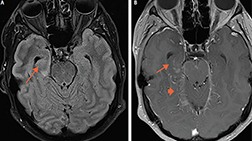

Cortical, juxtacortical lesions, and U-fiber lesions. Arrows: multiple small juxtacortical and cortical lesions throughout cerebral hemispheres. By definition, no white matter may interpose between a juxtacortical lesion and the cortex. Note U-fiber lesions along arcuate fibers in middle left frontal lobe, highly characteristic of demyelination and not seen in normal aging or vascular disease.